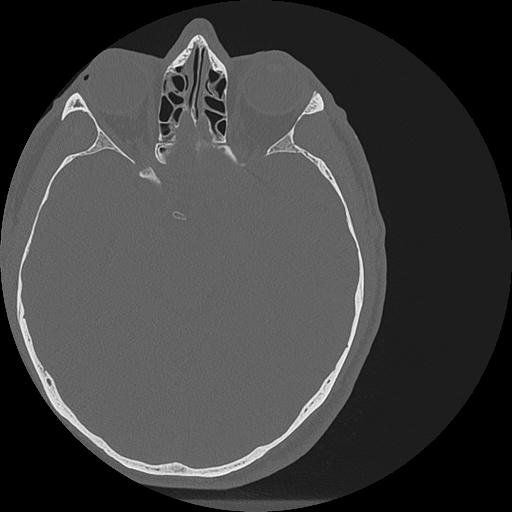

7 HUESO,,Vol,0.5,HUESO,,